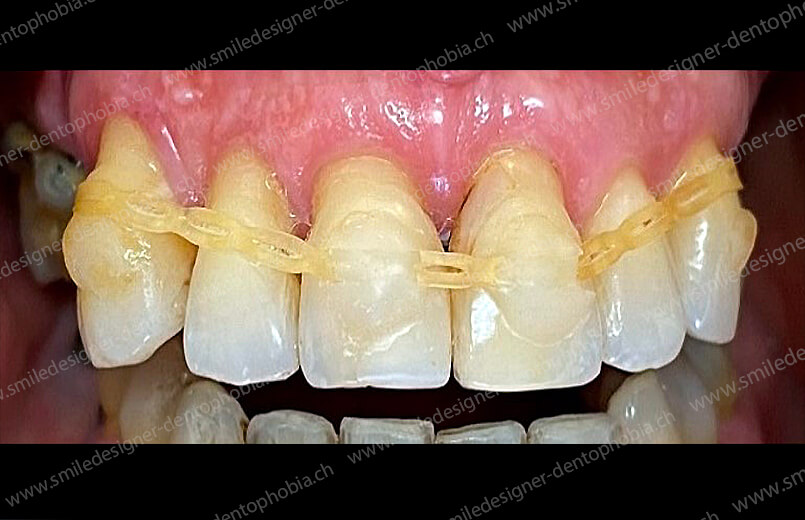

Cas clinique « GOLD STANDARD MCI » bi-maxillaire : Bridge implanto-porté sans extension (ALL ON 10). Version définitive des bridges avec un cosmétique en céramique.

Cas clinique « GOLD STANDARD MCI » bi-maxillaire : Bridge implanto-porté sans extension (ALL ON 8). Version définitive des bridges avec un cosmétique en céramique.